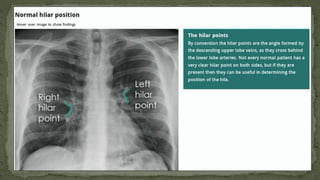

2. HILAR STRUCTURES

• Also called lung root, consists of the major bronchi and

pulmonary vessels (veins/arteries).

• The hila are not symmetrical but consist of the same basic

structures.

• The lymph nodes are also present but no visible unless

abnormal.